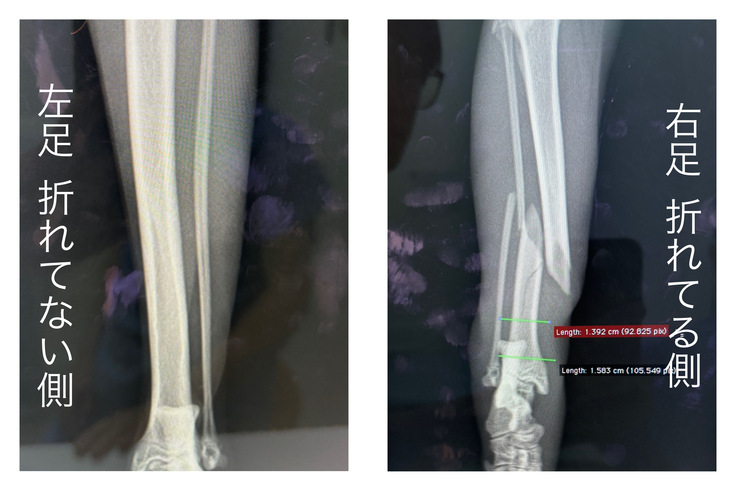

再度検査を受けた結果、右後ろ足の脛骨・腓骨の骨折と診断をうけ、手術と入院が必要だと判断されました。以下がレントゲンの写真になります。